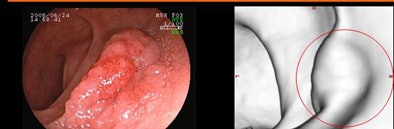

| Above, 23-mm adenoma (protruding lesion) in the rectum was seen at virtual colonoscopy (right). Below, 20-mm advanced adenoma (flat lesion) was detected only at conventional colonoscopy. All images courtesy of Dr. Kenichi Utano. |